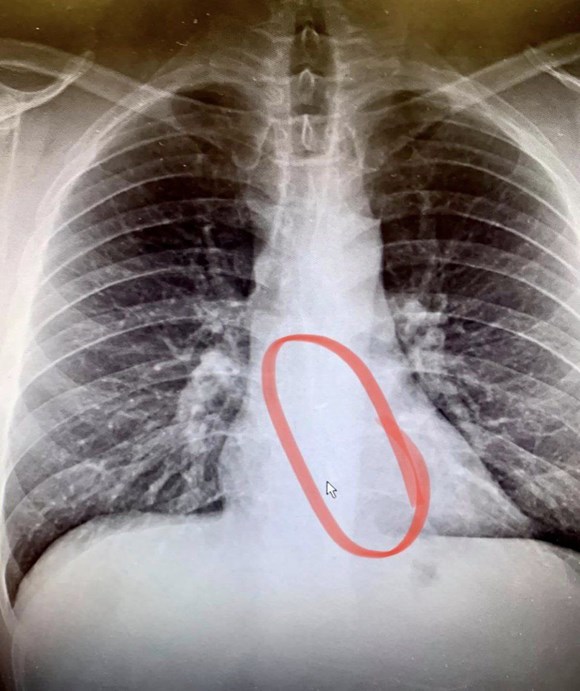

ABD'de boğaz kuruluğu şikayetiyle doktora giden adamın kablosuz kulaklığının tekini yuttuğu ortaya çıktı.